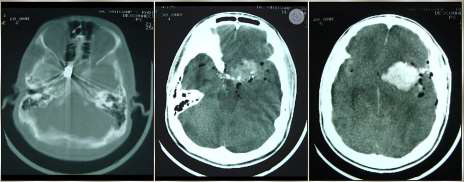

Paciente, 35 anos, sexo masculino, procedente de Recife-PE, é admitido em unidade de trauma, com história de agressão física por arma de fogo há 30 min. Veio trazido por policiais e sem profissional de saúde. Estava hipocorado, hipotérmico e possuía múltiplos orifícios de entrada de projétil de arma de fogo (PAF) em tórax, entrada e saída em região cervical e entrada em zigoma esquerdo. Apresentou parada cardiorrespiratória (PCR), revertida após 03 ciclos de reanimação cardiopulmonar, incluindo entubação orotraqueal sem sedação, expansão volêmica e drenagem torácica bilateral. Logo em seguida, após melhora hemodinâmica, não tinha abertura ocular e não tinha resposta motora, e pupilas estavam médio-fixas. De exame de imagem, fez apenas tomografia computadorizada (TC) de crânio.